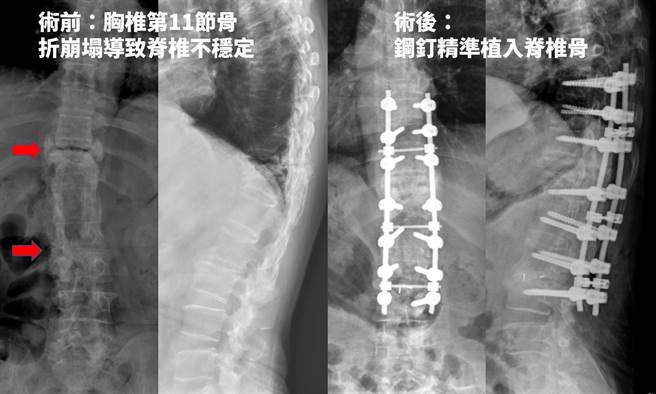

患者术前胸椎崩塌,经雷纳生脊椎机械手臂手术稳固脊椎。(光田综合医院提供/陈淑娥台中传真)

光田综合医院骨科医疗团队检查发现,她过往受伤的胸椎已塌陷到几乎看不见,原来纪女士曾在外院接受手术,仍觉得疼痛状况没有好转,因此在移除脊椎钢钉后,使正常2节胸椎垮到只剩1节高度,连带上下脊椎不稳定、压迫神经导致疼痛,背痛的情况日益加剧。

骨科医师许芳伟指出,一般来说脊椎压迫性骨折最快速有效治疗方法是「灌骨水泥」,但纪妇状况因骨头神经损伤严重致脊椎不稳定,因此为患者进行雷纳生脊椎机械手臂手术,辅助植入骨钉稳固脊椎,术后隔日疼痛立即缓解。